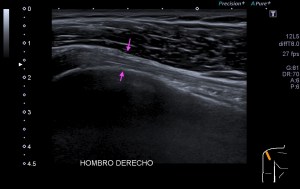

La radiografía revela aumento de las partes y se refrenda en la ecografía como puedes ver en la imagen aunque aún no hay afectación en el hueso en el caso que te presento hoy.

Ecografícamente y debido a su levedad, en el caso de hoy solo observamos cambios en las partes blandas de la cara lateral de la cabeza del quinto metatarsiano, este tejido se muestra heterogéneo, la cortical del hueso ligeramente prominente sin afectación de la misma.